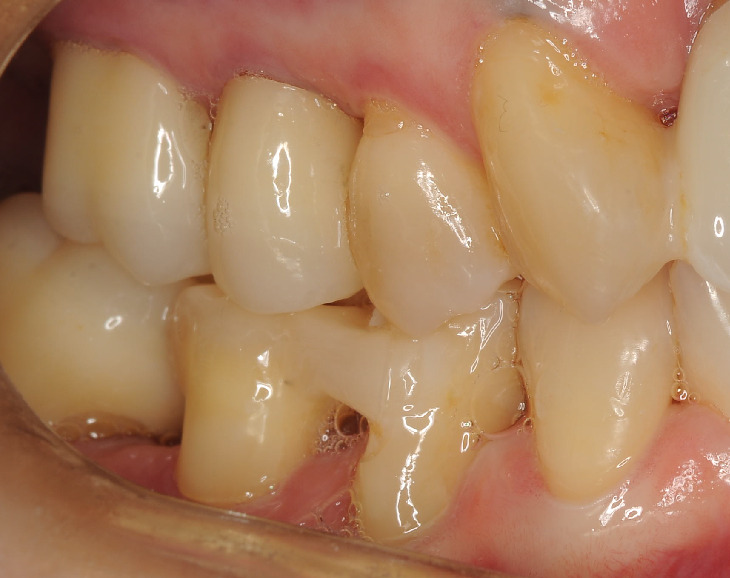

術後約1年

見て下さい!骨が再生しています。歯周ポケットも3mmまで回復。

患者さまと一緒に喜びました!!

勿論この治療、歯茎を切っていません。再生材料も使っておりません。

根の表面の顕微鏡によるクリーニングと血餅を安定させただけです。